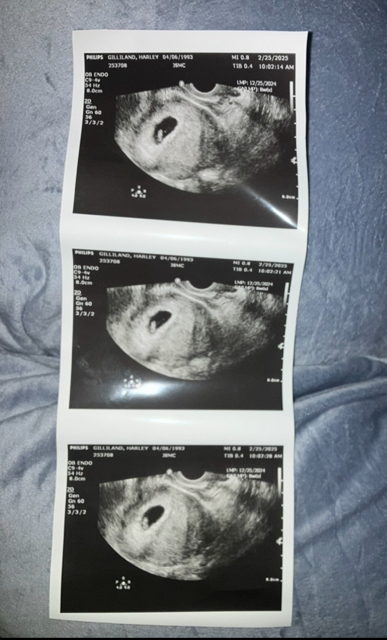

I do have pcos so my menstrual cycles are crazy long and irregular but in December I had two! Had 2 six day periods. 12/10–12/16 and 12/25–12/30. I’ve only had sex on 12/27 and 12/28. & I did have two day spotting on January 14–15. I have no idea why I took a pregnancy test on 2/10 but it was positive. Went to the health department the very next day on 2/11, I told them all this and they calculated that I conceived on 12/27. Went and had this ultrasound yesterday and I was thinking I was little over 10 weeks but nurse practitioner put my ga as 8w 6d and she baby looked more like 7 weeks. Anyway going by lmp the due date is 10/1 but ultrasound & nurse said 10/14. I only had sex while was on my period but by the estimated conception date, I don’t think any of the spem would still be alive. I don’t go back for another 4 weeks and I know this will be on my mind constantly. TIA for any input and for fun what is your gender guesses ?